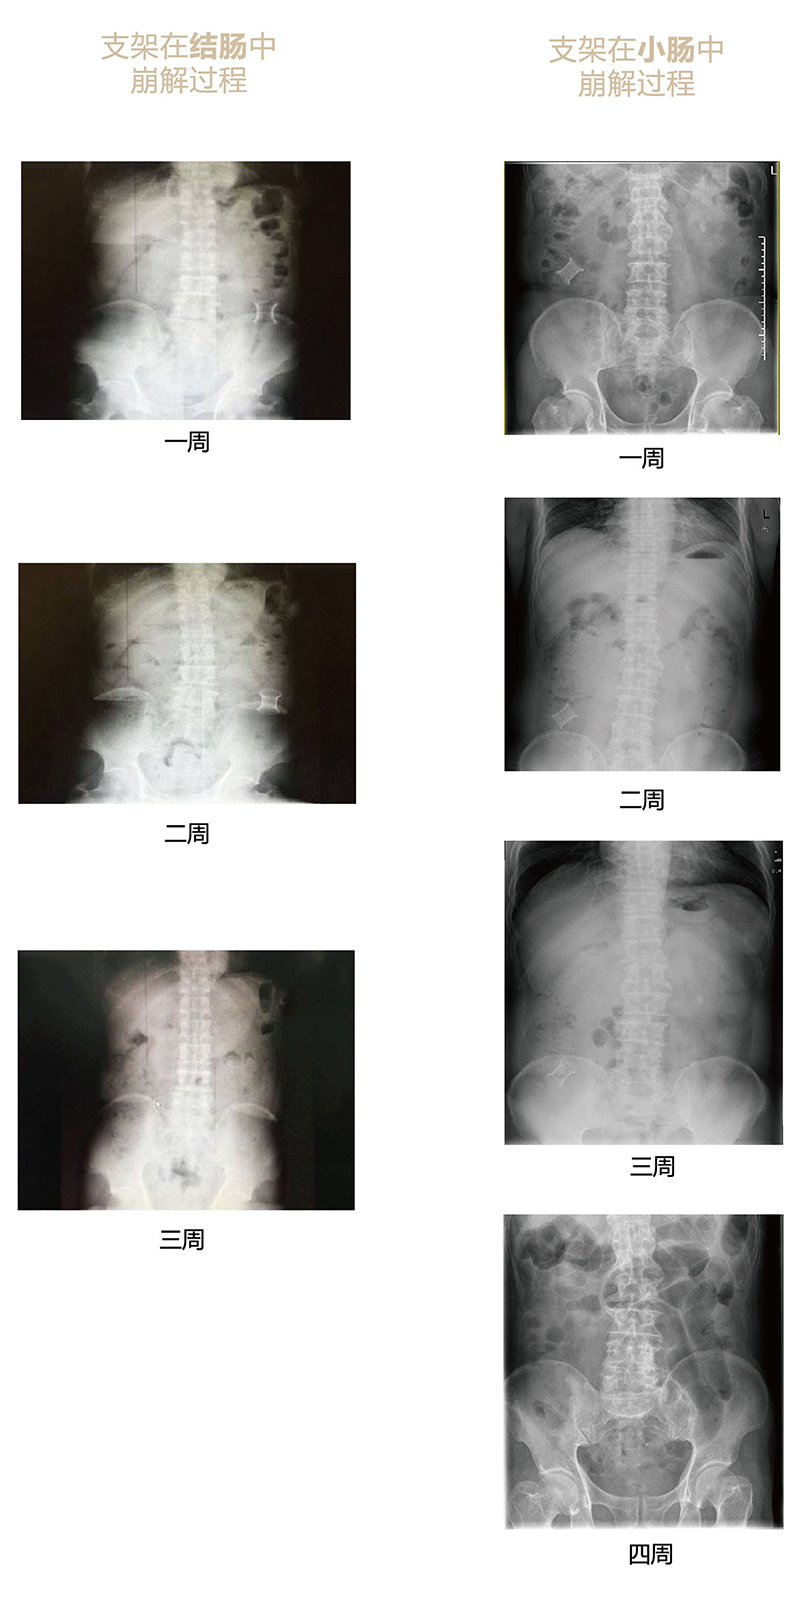

可崩解腸道吻合器由聚乙醇酸(PGA)與硫酸鋇按重量比7:1混合注塑制成,在X線下顯影,可動態(tài)追蹤可崩解腸道吻合器(支架)在腸道內(nèi)崩解過程。

手術(shù)崩解過程x光片-01.jpg

為解決該問題,蔡秀軍教授在“支架法空腔臟器吻合技術(shù)”的理念基礎(chǔ)上,又發(fā)明了“蔡氏腸轉(zhuǎn)流術(shù)”,這是一種應(yīng)用可崩解腸道吻合器HB型(可崩解腸轉(zhuǎn)流支架)(發(fā)明專利號:201910794214.3),的支架法腸道轉(zhuǎn)流術(shù),此創(chuàng)新術(shù)式既能保護(hù)低位吻合口,更避免了回納術(shù)??杀澜饽c轉(zhuǎn)流支架在直腸癌根治術(shù)中植入遠(yuǎn)端回腸,可確保完全阻斷腸腔,用腸造瘺管在轉(zhuǎn)流支架近端行腸造瘺,起到完全轉(zhuǎn)流的作用。腸轉(zhuǎn)流支架在二至三周內(nèi)逐漸崩解,并在四周內(nèi)完全排出體外,恢復(fù)腸道通暢后拔除造瘺管,避免了傳統(tǒng)造口回納的二次手術(shù)。該創(chuàng)新術(shù)式具有方法簡單、吻合時(shí)間短、人體內(nèi)無異物永久殘留、不破壞吻合口粘膜下血管,并能預(yù)防吻合口漏、可避免人工肛門留置及二次手術(shù)、治療周期可縮短至二至四周、患者生理心理創(chuàng)傷顯著減少。